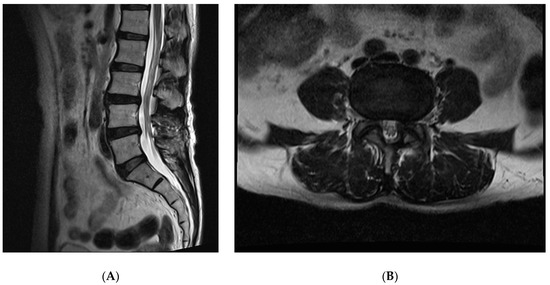

2. Case Report